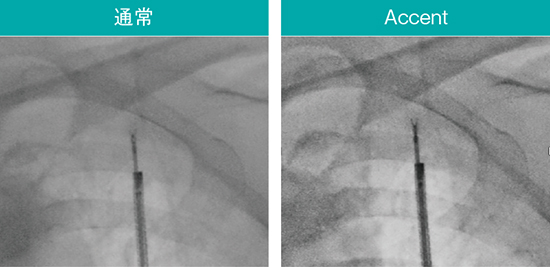

2.新画像処理条件「Accent」

内視鏡検査に用いるデバイスは通過性や柔軟性が優先され、透視下での視認性に課題がある製品もある。Ultimax-i の新画像処理条件「Accent」は、ガイドシースや生検針などのデバイスや関心領域を強調し、より手技がしやすい環境を提供する。実際の透視像(図7〜9)でも、Accent適用により腫瘤やEBUSプローブ、ガイドシース、ブラシなどのデバイスが明瞭に確認できる。

図7 AccentによるEBUSプローブや関心領域の強調

スコープ:BF-MP290、EBUS:UM-S20-17S(オリンパス社製)

図8 Accentによる鉗子や関心領域の強調

スコープ:BF-MP290、生検鉗子:FB-433D(オリンパス社製)

図9 Accentによるブラシや関心領域の強調

スコープ:BF-MP290、細胞診ブラシ:BC-205D-2010(オリンパス社製)